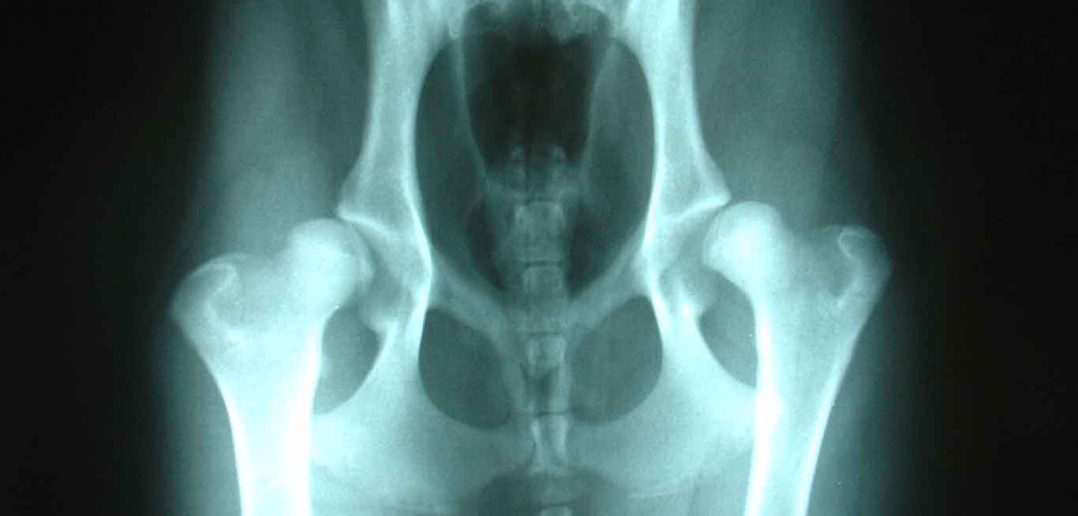

Initial assessment involves taking a history of the dog, and examining obvious clinical signs. The only real way to see if a dog is suffering from CHD is through X Rays. If found early enough in pups, surgery can correct the problem.

Featured Xray Image:

Joelmills [CC BY-SA 2.5, GFDL or CC-BY-SA-3.0], via Wikimedia Commons